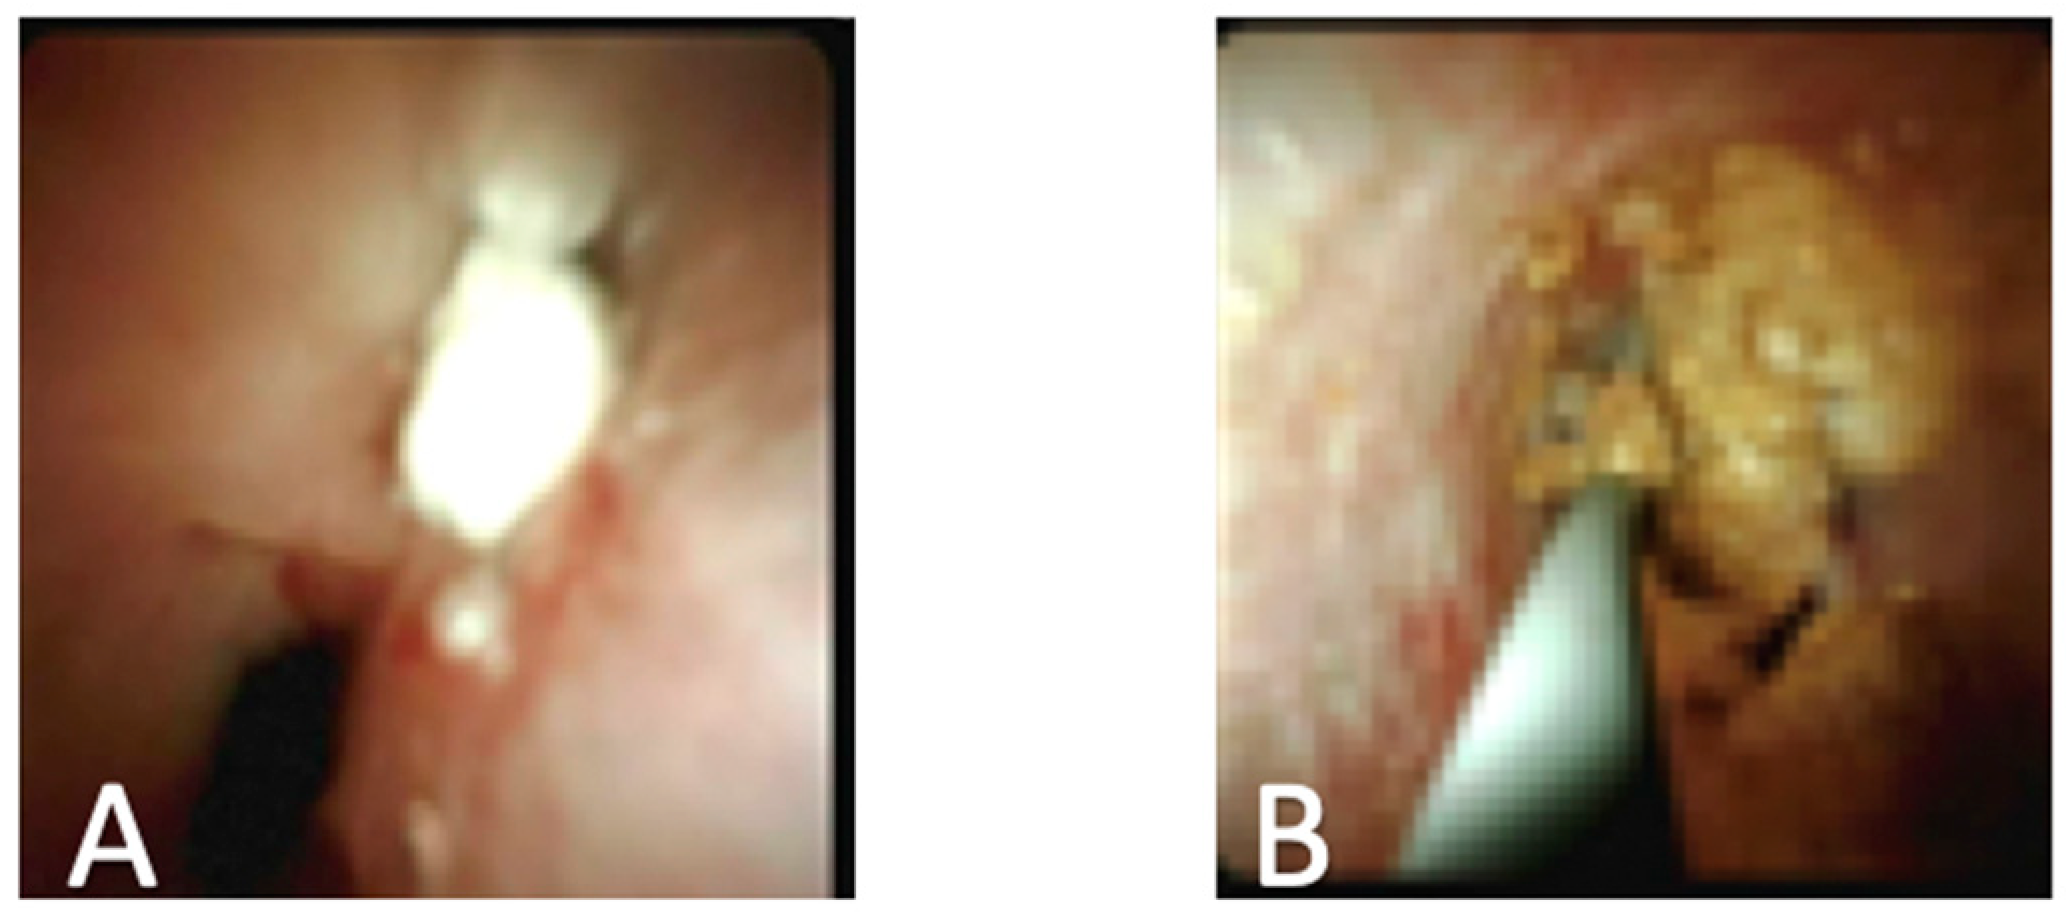

4. Cholangioscopy in Primary Sclerosing Cholangitis

- Sandha, G.; D’Souza, P.; Halloran, B.; Montano-Loza, A.J. A Cholangioscopy-Based Novel Classification System for the Phenotypic Stratification of Dominant Bile Duct Strictures in Primary Sclerosing Cholangitis-the Edmonton Classification. J. Can. Assoc. Gastroenterol. 2018, 1, 174–180. [Google Scholar] [CrossRef] [PubMed]

| Evaluation of strictures |

| Visually guided biopsy |